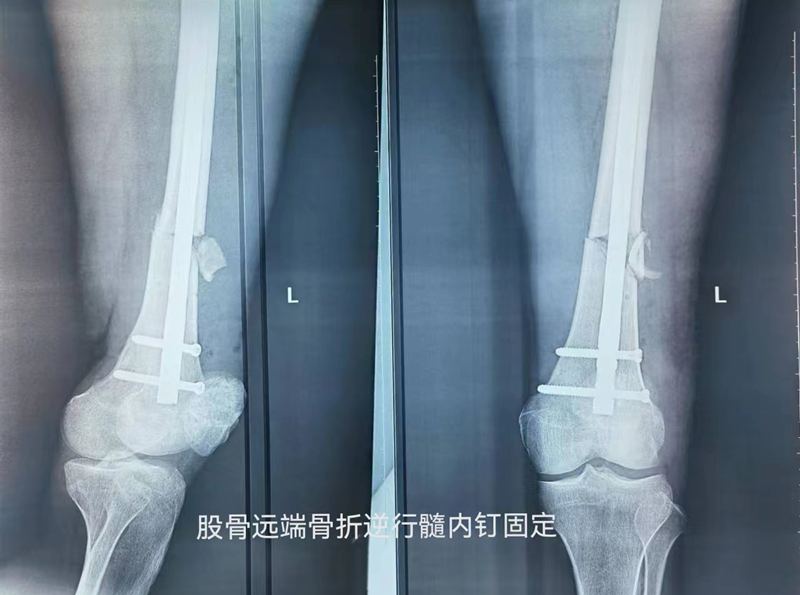

骨二科韩双阳主治医师为患者详细检查。患者左大腿远端畸形、肿胀、淤青伴疼痛,不能站立及行走。CT检查显示为左股骨远端骨折。韩医生报请孙笛主任共同制定手术方案,因骨折的部位位于股骨远端决定实施左股骨干骨折闭合复位倒打髓内钉内固定术。这种术式为患者的骨折可起到非常稳定的固定作用,经过一列术前准备,孙笛主任与韩医生共同为患者进行了手术。

手术由韩双阳主治医师主刀,摆手术体位、切口、确认进针点位置、牵引复位骨折端、使用“金手指”辅助穿插过骨折端等,韩医生认真仔细的熟练完成每一个操作步骤,由于患者股骨远端髓腔宽大,骨折部位存在轻度横向移位,同时使用阻挡钉技术辅助复位,顺利逆行置入髓内钉经C型臂透视示骨折对位对线良好,主钉及螺钉位置良好。韩双阳医生每个步骤都体现了患者至上,认真负责的专业精神。手术顺利完成,而且做到了骨折端不切开闭合复位可利于患者以最快的速度达到骨愈合作到微创精准治疗。